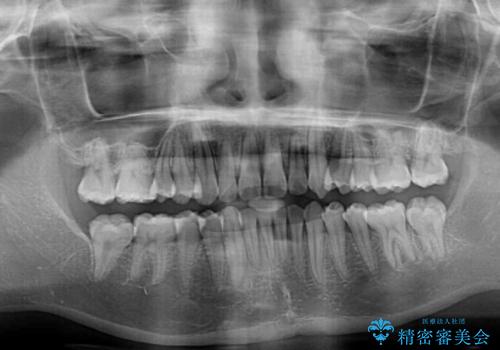

クロスバイト改善中には歯髄壊死を起こすリスクがあるため、神経に問題がないか確認しながら治療を進めて行く必要があります。

思っていたよりも早くクロスバイトは改善され、歯髄壊死に至ることなく、無事に治療を終えることができました。